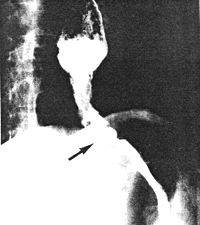

Case 35.4V.M., male aged 38 years. Radiographic examination showed constant irregularity and narrowing of the lower 4.0 cm of the oesophagus, extending through the hiatus to the gastro-oesophageal junction (Fig. 35.4). The diagnosis of carcinoma was confirmed by oesophagoscopy. Constant contraction of the pyloric sphincteric cylinder, similar to that of the previous cases, was present.

| Fig. 35.4. Case V.M. Carcinoma lower oesophagus, extending through hiatus in diaphragm (arrow). |